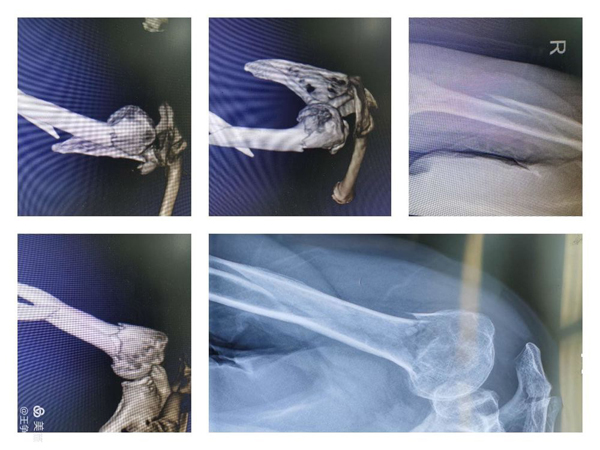

近日,二一五医院骨科医院创伤骨科收治了一例高龄肱骨多段骨折的病人。83岁的女性患者因跌倒致肱骨外科颈、肱骨干粉碎骨折。入院后在和患者家属反复沟通后,决定行右肱骨骨折的复位及内固定手术。但是由于患者骨折比较特殊,按照以往的治疗方法,需要对肱骨近端和肱骨干分别进行处理,需要两套内固定器材,这使患者的创伤及经济压力都大大增加。

针对患者具体情况,郭永良主任带领科室医师团队反复讨论,最终选择了一种相对简单、微创、并且比较经济的治疗方法——肱骨“专家级”髓内钉,俗称“降落伞”髓内钉对患者进行手术。这种特殊的髓内钉设计独特,能有效固定这种多段粉碎骨折,其远端和近端有多枚、多方向不同的锁定孔,可根据骨折的具体情况进行选择使用。

手术由王争刚主任医师、吴超副主任医师主刀,在全身麻醉下进行,考虑到肱骨干部骨折位于中下段,闭合复位困难,并且有桡神经损伤风险,故术中干部骨折予以有限切开、确保桡神经安全,肱骨外科颈骨折完全闭合操作,避免影响对骨折断端血液循环,将大大缩短骨折愈合时间。

图片为术中透视及术后外观照。

通过一套内固定器械,完成多段复杂骨折,并且全程在微创理论指导下进行,目前患者已经下地活动,术后恢复效果良好。